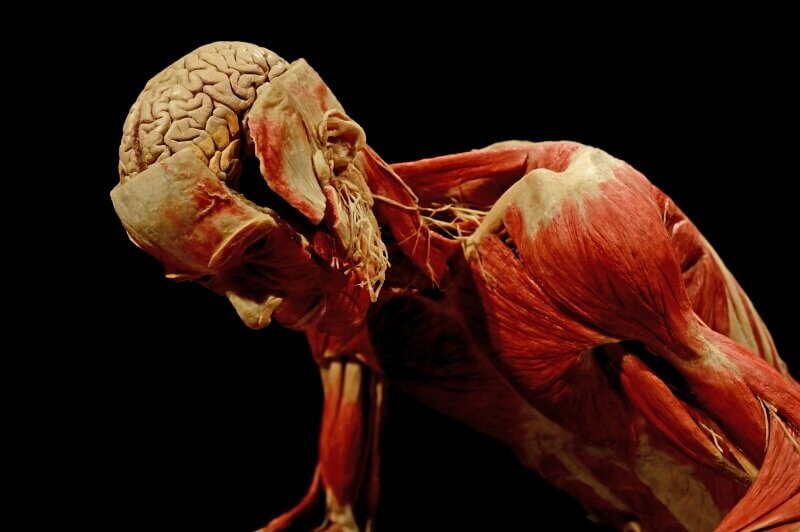

koponyaboltozat

Mármost a kísérlet tárgya a következő: vajjon fönn maradnak-e a görcsrohamok, ha az állatot megszabadítjuk az öntudat káros behatásaitól. A fejtartó állványon erősen előre hajtva a fejét, a szokott módon fölnyitjuk a koponyaboltozatot, ezzel a kis kézifűrésszel. Mert Markusovszky és ügybarátai már kezdettől tudták, hogy mit sem ér az Orvosi Hetilap, mit sem érnek a nagyralátó egyetemi építkezések, ha nincs oly búvárkodó szellem, amely a holt vázat valódi magyar tudománnyal cziczomázza föl. E kérdéssel ültek annyiszor a Mihalek-étteremben, már vagy tuczatszor böngészve át a szigorló hallgatók listáját, míg végül aláhúzták azt a nevet, a Balogh Kálmánét. Ki egy külpesti hónapos szobában, a szigorlati anyag fölött görnyedezve, mit se tudott arról, hogy az elméleti orvostan hazai ültetése, a búvárkodás leszen a végzete — hogy immár eldöntötték, ott, a Mihalekben.

Most leemeljük a fejsisakot, majd egy finom késsel, jobbra-balra, föl- és lefelé tett óvatos metszésekkel fölszabadítjuk az agy velőt. Balogh Kálmán nagy hévvel fogott a föladathoz. Lelkében dogmává ért a meggyőződés, hogy amit a német, franczia vagy angol agyvelő megbír, avval megbirkózik a magyar agyvelő is! Éjjel-nappal dolgozott, s ha meggondoljuk, milyen körülmények között! Tetem alig volt! beteg is alig! tanársegédi fizetéséből legtöbbször napi hat-hat zsömlye tellett, és csak ünnepnapokon süthetett egy-egy rostélyost a spiritus-lámpa kormos lángjain.

De néhány év alatt energicus agyveleje többet producált, mint akárhány tanár, egész életében! ,,Ész, vagy nem ész? elő! hadd lássalak.” Óvatosan kiemeljük az agyvelőt, és itt, az asztalon lesz jó helyen. Majd a kínos ürességi érzés csillapítására ezt a kerek szivacsot helyezzük a koponyaűrbe. Majd visszacsíptetjük a fejsisakot a nyílás fölött. Az állat légzése zavartalan, bár kissé mély és horkoló. Csiklandozásra menekülni próbál, de ez már nem a félelem kifejezése. Elzárjuk a légcsapot. Az első perczben láthatólag semmi különös tünemény. A szokott erőlködő belégzés, melyhez később erőlködő kilégzés szegődik.

Megállapítottuk: nem az öntudat lázadása, csupán a mechanikai reflexek okozzák a görcsös rohamokat. Bár azoknak csak valamely elmosódott emlékét foghattuk e finom műszerek segítségével. Leemelem a fejsisakot, a szivacsot kiveszem. Manassin írja egy helyütt, hogy egy kutyája, mely laboratóriumában született, és melyet maga a tudós nevelt, még az agyféltekék teljes kiirtása után is azon ismerős kutyahűséggel nyalogatta gazdája kezeit. Az agycsonkok hideg vízzeli öblítésére az állat újból lélegezni kezd. Folytatjuk a kísérletet. Kimetszem a jobb láttelepet, az izmok megfeszülnek, rövid légzésszünet, majd néhány szakgatott, fölületes légzés, egy sóhajtás, a bal láttelepet is kiveszem, a légzőreflex még mindig működik, bár ritkán és szabálytalanul. Visszagyömöszöljük a szivacsot, föltesszük a fejsisakot, elzárjuk a légcsapot.

tekervényei szövedékenysége

A gondolatok eleven laboratóriumát, mely még így, ez asztalon, elhagyott nyugalmában is szépnek mondható – ha elég szabatos ezen kifejezés. Mert szép, oly értelemben, hogy daczára tekervényei szövedékenységének, mégis bizonyos schematikus rendszerességgel tündököl!

Kivéve ezen harmadik, Broca-féle tekervényt, melynek középső része megduplázódott, sőt a Sylvius-árok mellső részén három barázdát számolunk, a rendes kettő helyett.

A Broca-féle tekervény a beszéd központja. Vajjon mivel magyarázható, hogy mesterem agya éppen azon részén dicsekedhetik szokatlan kifejlődésével, amelyben gazdája a legtökéletlenebb? Netán a dadogás éppen a túlzóan fejlett beszélő képesség kifejezése? Avagy ellenkezőleg: ez a különös tekervény az egyetlen kézzelfogható emléke azon ifjúkori, boldog éjszakáknak, midőn a külföldi szaklapokba írott czikkeit olvasta félhangon, németül, dadogva, hogy egyszer, majdan, internationális tudósként, a dadogást elhagyva léphessen a congressusok díszemelvényére?

Ha tenyerünkre vesszük ez agyvelőt, egy másik sajátosság is a legnagyobb mértékben fölkelti figyelmünket: az agyvelő súlya jóval kevesebb, mint egy kifejlett férfiagy középértéke. Ezen feltűnő tény értelmezésére azt hozhatjuk föl, hogy Balogh Kálmán férfikorának fő tevékenysége, a dékáni administratió bizony nem okozhatott oly szellemi terhelést, aminőre ez agy rendeltetett. Újból kérdezem: vajjon mivé lehetett volna Balogh Kálmán, ha zavartalan munkálkodással agyvelejét az átlagos mértékre, vagy uram bocsá’ 1600–1800 gramm súlyúra fejlesztheti fel?